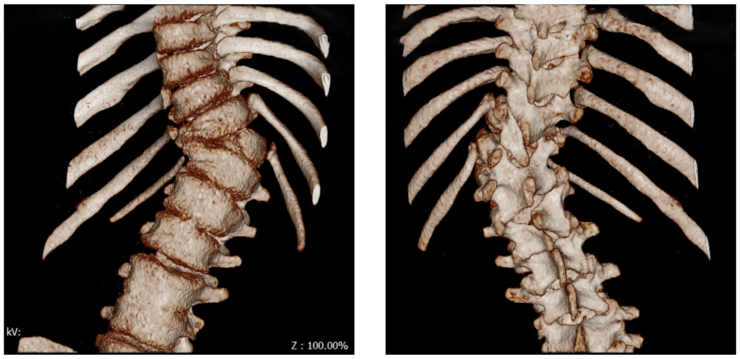

Rechtskonvexe Thorakalskoliose bei einem 15 jährigen Mädchen:

Bei einer kongenitalen Skoliose wird oft noch eine Computertomographie mit 3D Rekonstruktion durchgeführt, damit man genau sehen kann, welche Knochen fehlgebildet oder verwachsen sind. Hiervon hängen die Progressionswahrscheinlichkeit und die OP-Methode ab.